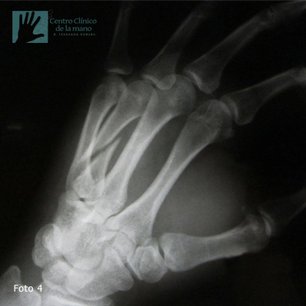

Fractura del Metacarpiano